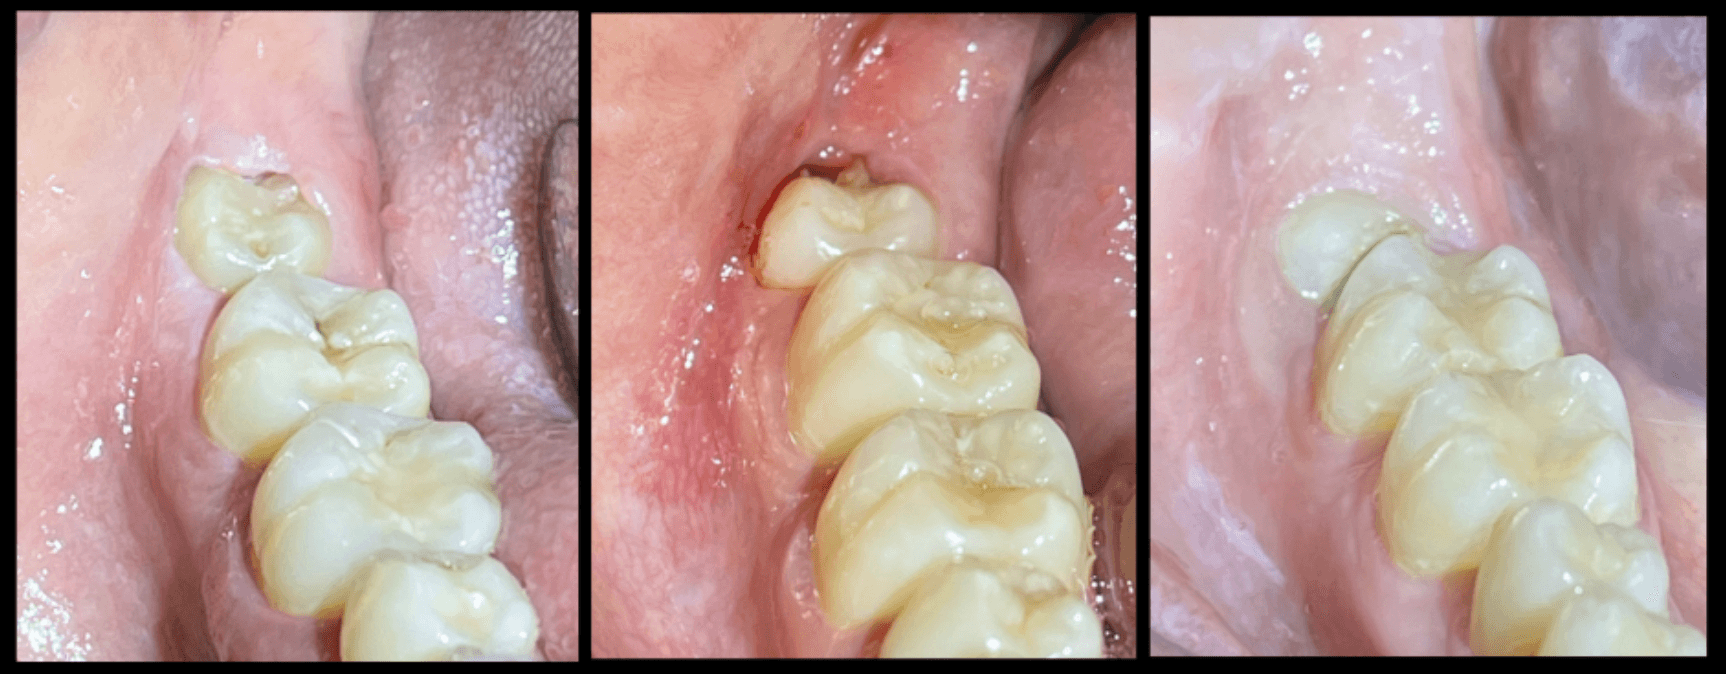

플란트구강악안면외과치과는 자연치아 보존을 최우선으로 생각하며, 불필요한 발치 없이 치아 수명을 연장하는 보존 치료를 우선합니다.

단순히 치아를 살리는 것보다 '얼마나 오래 건강하게 사용할 수 있는지'를 더욱 중요하게 판단합니다. 예후가 좋은 치아는 정성을 다해 보존 치료에 힘쓰지만, 장기적으로 좋지 않다면 무리하게 살리기보다 더 나은 결과를 위한 치료를 고려합니다. 불가피하게 수술이 필요할 경우, 환자분이 편안하게 최선의 결과를 얻으실 수 있도록 노력합니다. 환자의 입장에서 먼저 생각하는 것, 이것이 플란트구강악안면외과치과의 핵심 진료 철학입니다.

플란트구강악안면외과치과는 자연치아 보존을 최우선으로 생각하며, 불필요한 발치 없이 치아 수명을 연장하는 보존 치료를 우선합니다. 단순히 치아를 살리는 것보다 '얼마나 오래 건강하게 사용할 수 있는지'를 더욱 중요하게 판단합니다. 예후가 좋은 치아는 정성을 다해 보존 치료에 힘쓰지만, 장기적으로 좋지 않다면 무리하게 살리기보다 더 나은 결과를 위한 치료를 고려합니다. 불가피하게 수술이 필요할 경우, 환자분이 편안하게 최선의 결과를 얻으실 수 있도록 노력합니다. 환자의 입장에서 먼저 생각하는 것, 이것이 플란트구강악안면외과치과의 핵심 진료 철학입니다.